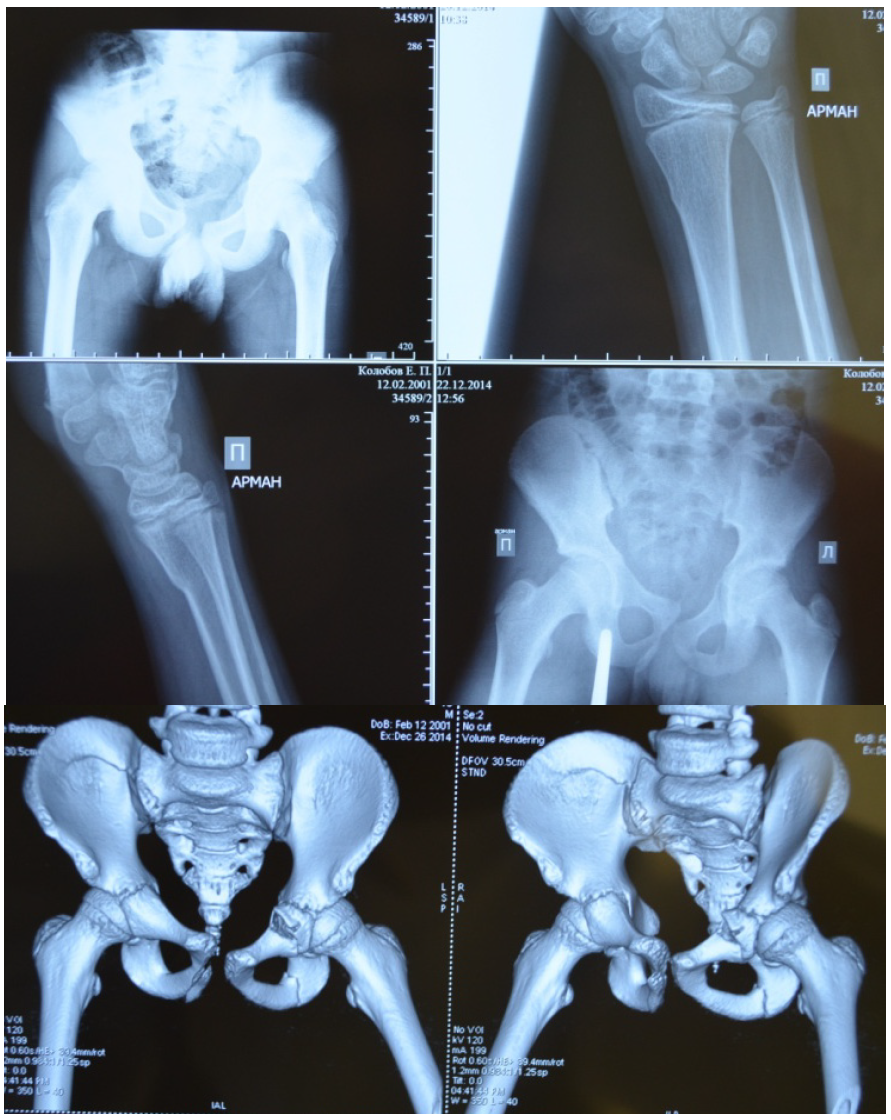

Характер травмы нередко заставлял нас заподозрить гораздо более серьезные повреждения, чем отражают обычные рентгенограммы. Так, под нашим наблюдением был пациент после сочетанной травмы в результате наезда автомобиля в колее в зимнее время, что вызвало раздавливание таза, сопутствующий перелом лучевой кости, черепно-мозговую травму (сотрясение головного мозга). Характер повреждения таза был уточнен через 9 дней после травмы при поступлении больного в клинику с вынужденным положением левого бедра и сильным болевым синдромом (рис. 3).

Больной оперирован на фоне установившейся эутонии. С помощью аппарата Илизарова со стержневой фиксацией было восстановлено тазовое кольцо, одновременно проведено открытое вмешательство с репозицией среднего фрагмента вертлужной впадины, фиксацией спицами (рис. 4).

Рис. 3. Больной К., 13 лет. Травма с раздавливанием таза под колесами автомобиля. Диагноз уточнен при спиральной компьютерной томографии: оскольчатый внутрисуставной перелом вертлужной впадины слева, нарушение переднего тазового кольца

Рис. 4. Больной К., рентгенограммы и внешний вид после оперативного лечения